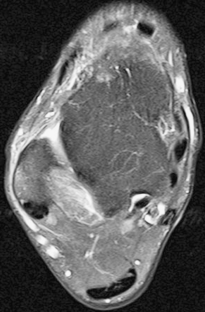

Fig. 4